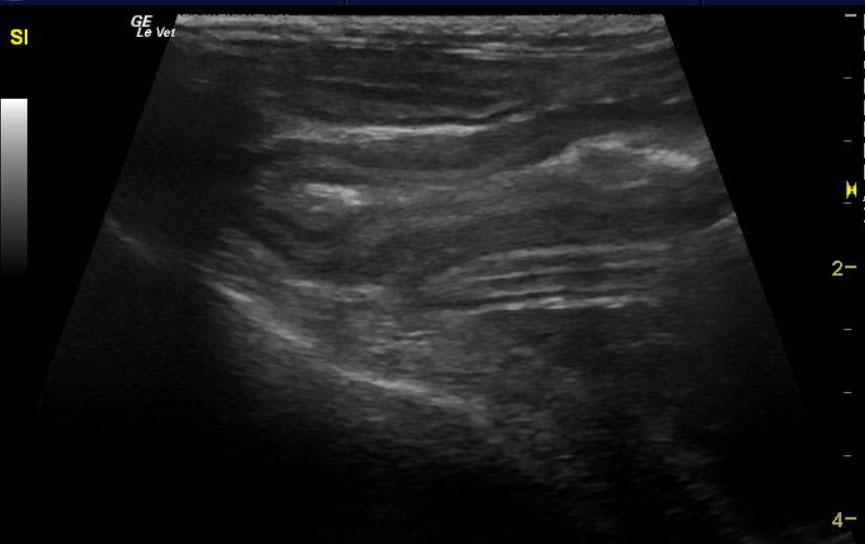

Image Interpretation

The spleen was enlarged and micronodular with slight scalloping contour. The spleen measured 1.33 cm. The mesenteric root lymph nodes were enlarged at 0.62 cm with reactive surrounding fat. Other mesenteric root lymph nodes measured 1.4 x 2.0 cm with reactive fat. Slight free fluid was noted owing to lymphatic strangulation. The remainder of the bowel revealed increased muscularis to mucosa thickening with a 2:1 ratio.